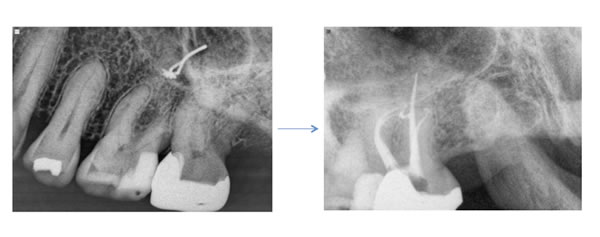

Case by Dr. Adam Monroe

How deep? I prefer to use an ultrasonic tip to trough apically for the canal. A MUNCE bur (CJM Engineering) is also very helpful. These burs are tapered such that it is easy to visualize the tip of the bur contacting the dentin when viewed through the microscope or under high magnification. Copious amounts of water and frequent clearing of the field are very important so that we do not lose our orientation. Try to visualize the pulpal floor and stay away from the furcation. Once you have troughed three-four mm apically, stop and ensure you have remained mesial to the furcation. Staining the floor with Toulidine Blue can help highlight the pulpal floor anatomy.

First Files? When the canal orifice is located. I prefer to use a six C plus file with a small bend to delicately negotiate the canal. Angle the file from the distal in order to gain an easier glide path down the root. Do not move up to larger files until the 6 and 8 pass easily down the canal. The path of the canal often takes a sharp mesial and buccal turn in the coronal third of the root. Considering this acute curvature, be careful with orifice openers or stiff files early in the procedure.